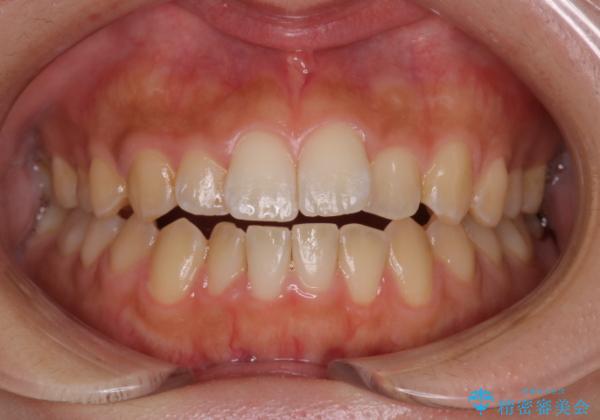

- 前歯の叢生を主訴に来院されました。非抜歯でインビザラインで治療をしました。

叢生はIPRをし、並べました。この患者様はオープンバイトだったため歯を並べる過程でかみ合わせも治しました。